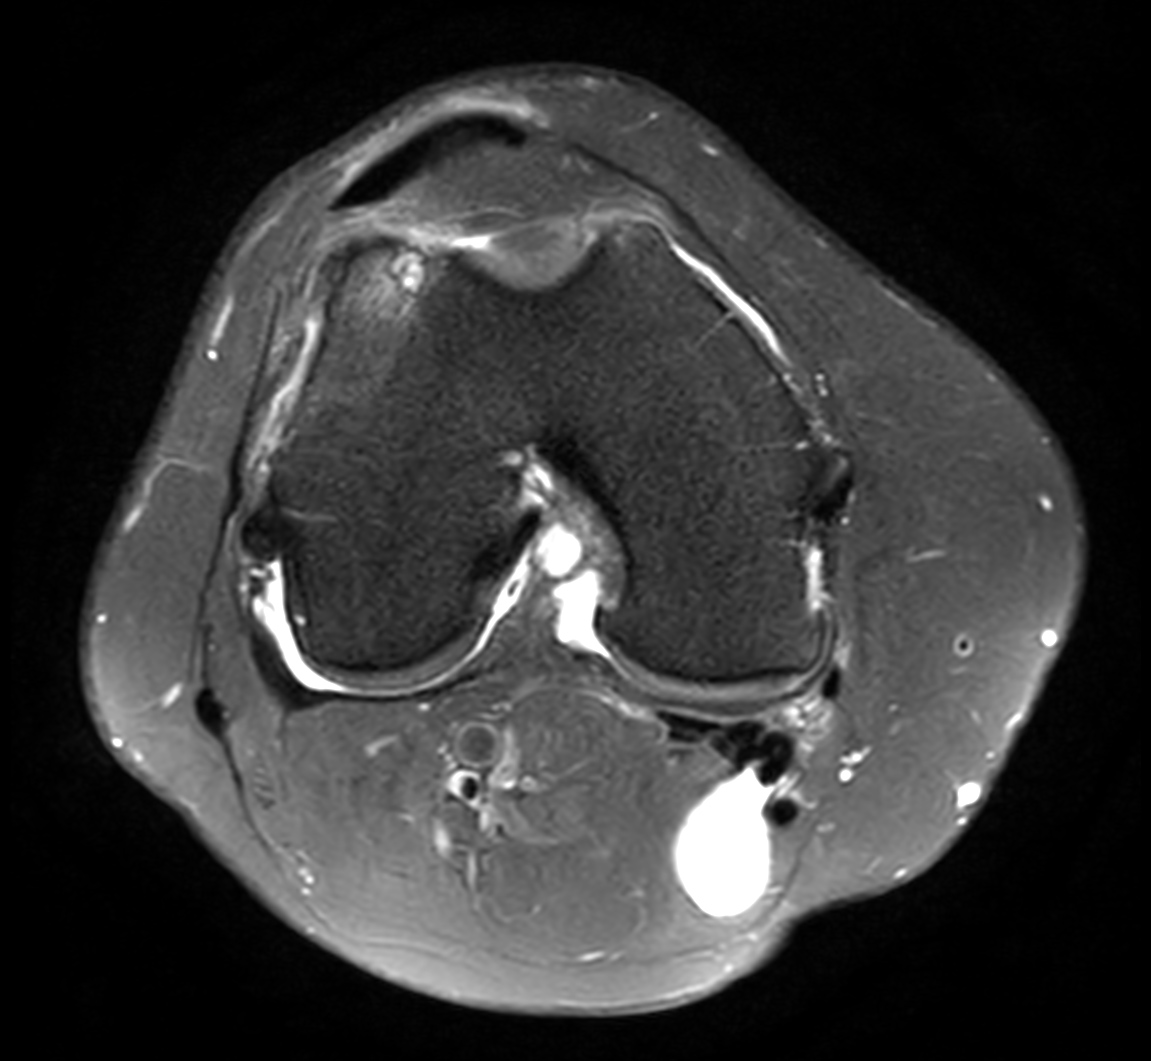

Axial PDw SPIR